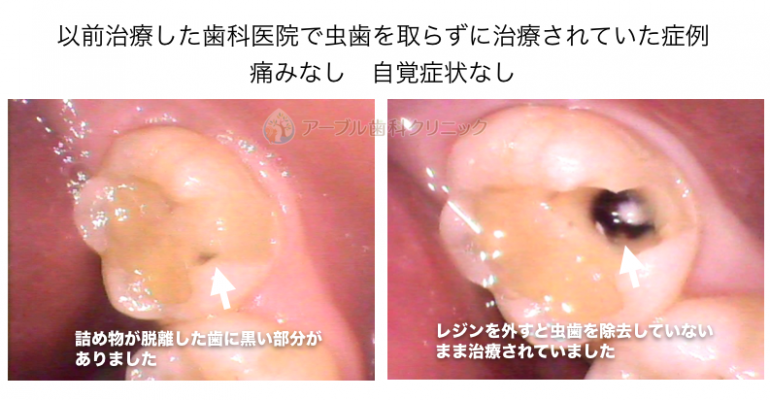

以前治療したレジン治療の内部から虫歯の取り残しが見つかった症例

レジン治療の内部で虫歯の取り残しがあった症例